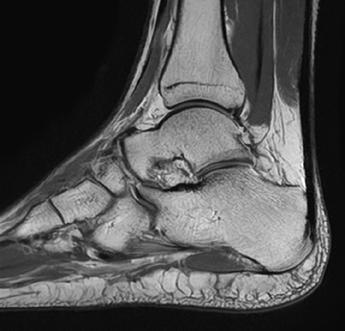

The power of MRI to pick up subtle injuries

Even the smallest injury in elite sports has implications. Having the right diagnostic tool at the peak of its development is vital to diagnosing subtle injuries that could impact player health. Using high resolution MRI therefore helps to identify very minute intra-articular joint injuries, muscle oedema changes or very small fibre tears (see fig 2).

Detailed diagnostic information is crucial to then accurately give the injury a grading using classification systems4 This grading severity then translates into an estimate of the mean number of player and training days that will be lost.

Fig 2: Very small fibre tears identified using high resolution MRI